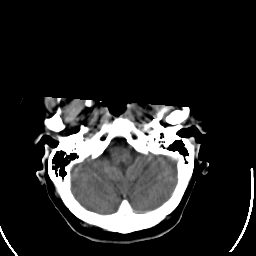

Stroke CT #2 -- Slice #3

[Home][Help][Clinical] Slice 3